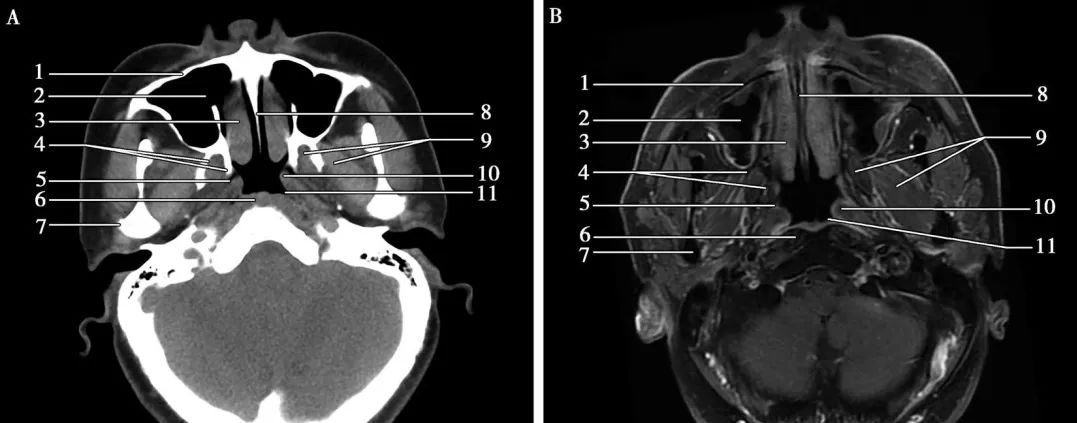

▲橫斷面(miàn)-鼻咽層面(miàn) A.CT;B.MRI

鼻咽癌表現爲鼻咽部軟組織腫塊,病竈大小不等,早期腫塊不明顯,僅表現爲咽隐窩變淺,腭帆提肌腫脹,晚期表現爲突出鼻咽腔的腫塊,大者可占滿鼻咽腔,形态不規則,可侵犯鄰近結構,沿顱底孔道(dào)蔓延至顱内。影像學(xué)檢查對(duì)确定腫瘤侵犯範圍及與周圍重要結構的關系十分關鍵。在區别腫瘤和軟組織,評估淋巴結轉移,觀察腫瘤沿神經(jīng)擴散和骨髓受累方面(miàn),增強MRI優于CT掃描。CT掃描可以更好(hǎo)地顯示早期顱底骨質破壞和其他的骨質破壞征象。

CT表現:鼻咽癌局限在黏膜間隙時(shí),CT表現爲鼻咽腔兩(liǎng)側不對(duì)稱,局部黏膜增厚,一側咽隐窩變淺或消失,腭帆提肌、腭帆張肌腫脹,脂肪間隙消失。可引起(qǐ)周圍結構的侵犯:向(xiàng)前侵犯鼻腔,達翼腭窩,向(xiàng)兩(liǎng)側侵犯咽旁間隙,向(xiàng)後(hòu)侵犯咽後(hòu)間隙以及椎前肌,向(xiàng)下侵犯口咽軟腭和扁桃體,向(xiàng)上侵犯斜坡及顱底骨質,通過(guò)顱底孔道(dào)進(jìn)入顱内。鼻咽癌常并發(fā)頸部淋巴結腫大。CT增強掃描,腫塊輕度強化,邊界不清(下圖)。

▲鼻咽癌CT表現

鼻咽左側頂後(hòu)壁及左側壁腫物,大小約1.8cm×2.7cm,呈中等強化,左側咽隐窩消失。腫物局限于鼻咽腔,未侵犯咽旁間隙。顱底未見骨質破壞。

MRI表現:MRI顯示腫瘤範圍、周圍結構侵犯以及頸部淋巴結腫大與CT基本相同,因MRI軟組織分辨率較CT高,所以MRI能(néng)更早的發(fā)現病變,并準确地顯示病變部位、大小、範圍及浸潤深度。T1WI上腫塊相對(duì)于肌肉呈低-等混雜信号,T2WI呈較高信号,增強後(hòu)輕度強化(下圖)。

▲鼻咽癌MRI表現

鼻咽左側頂後(hòu)壁及左側壁軟組織增厚,範圍約1.9cm×2.3cm,T1WI呈等信号,T2WI/FS呈中高信号,DWI擴散受限,增強明顯強化,左側咽隐窩消失。右側咽隐窩存在。